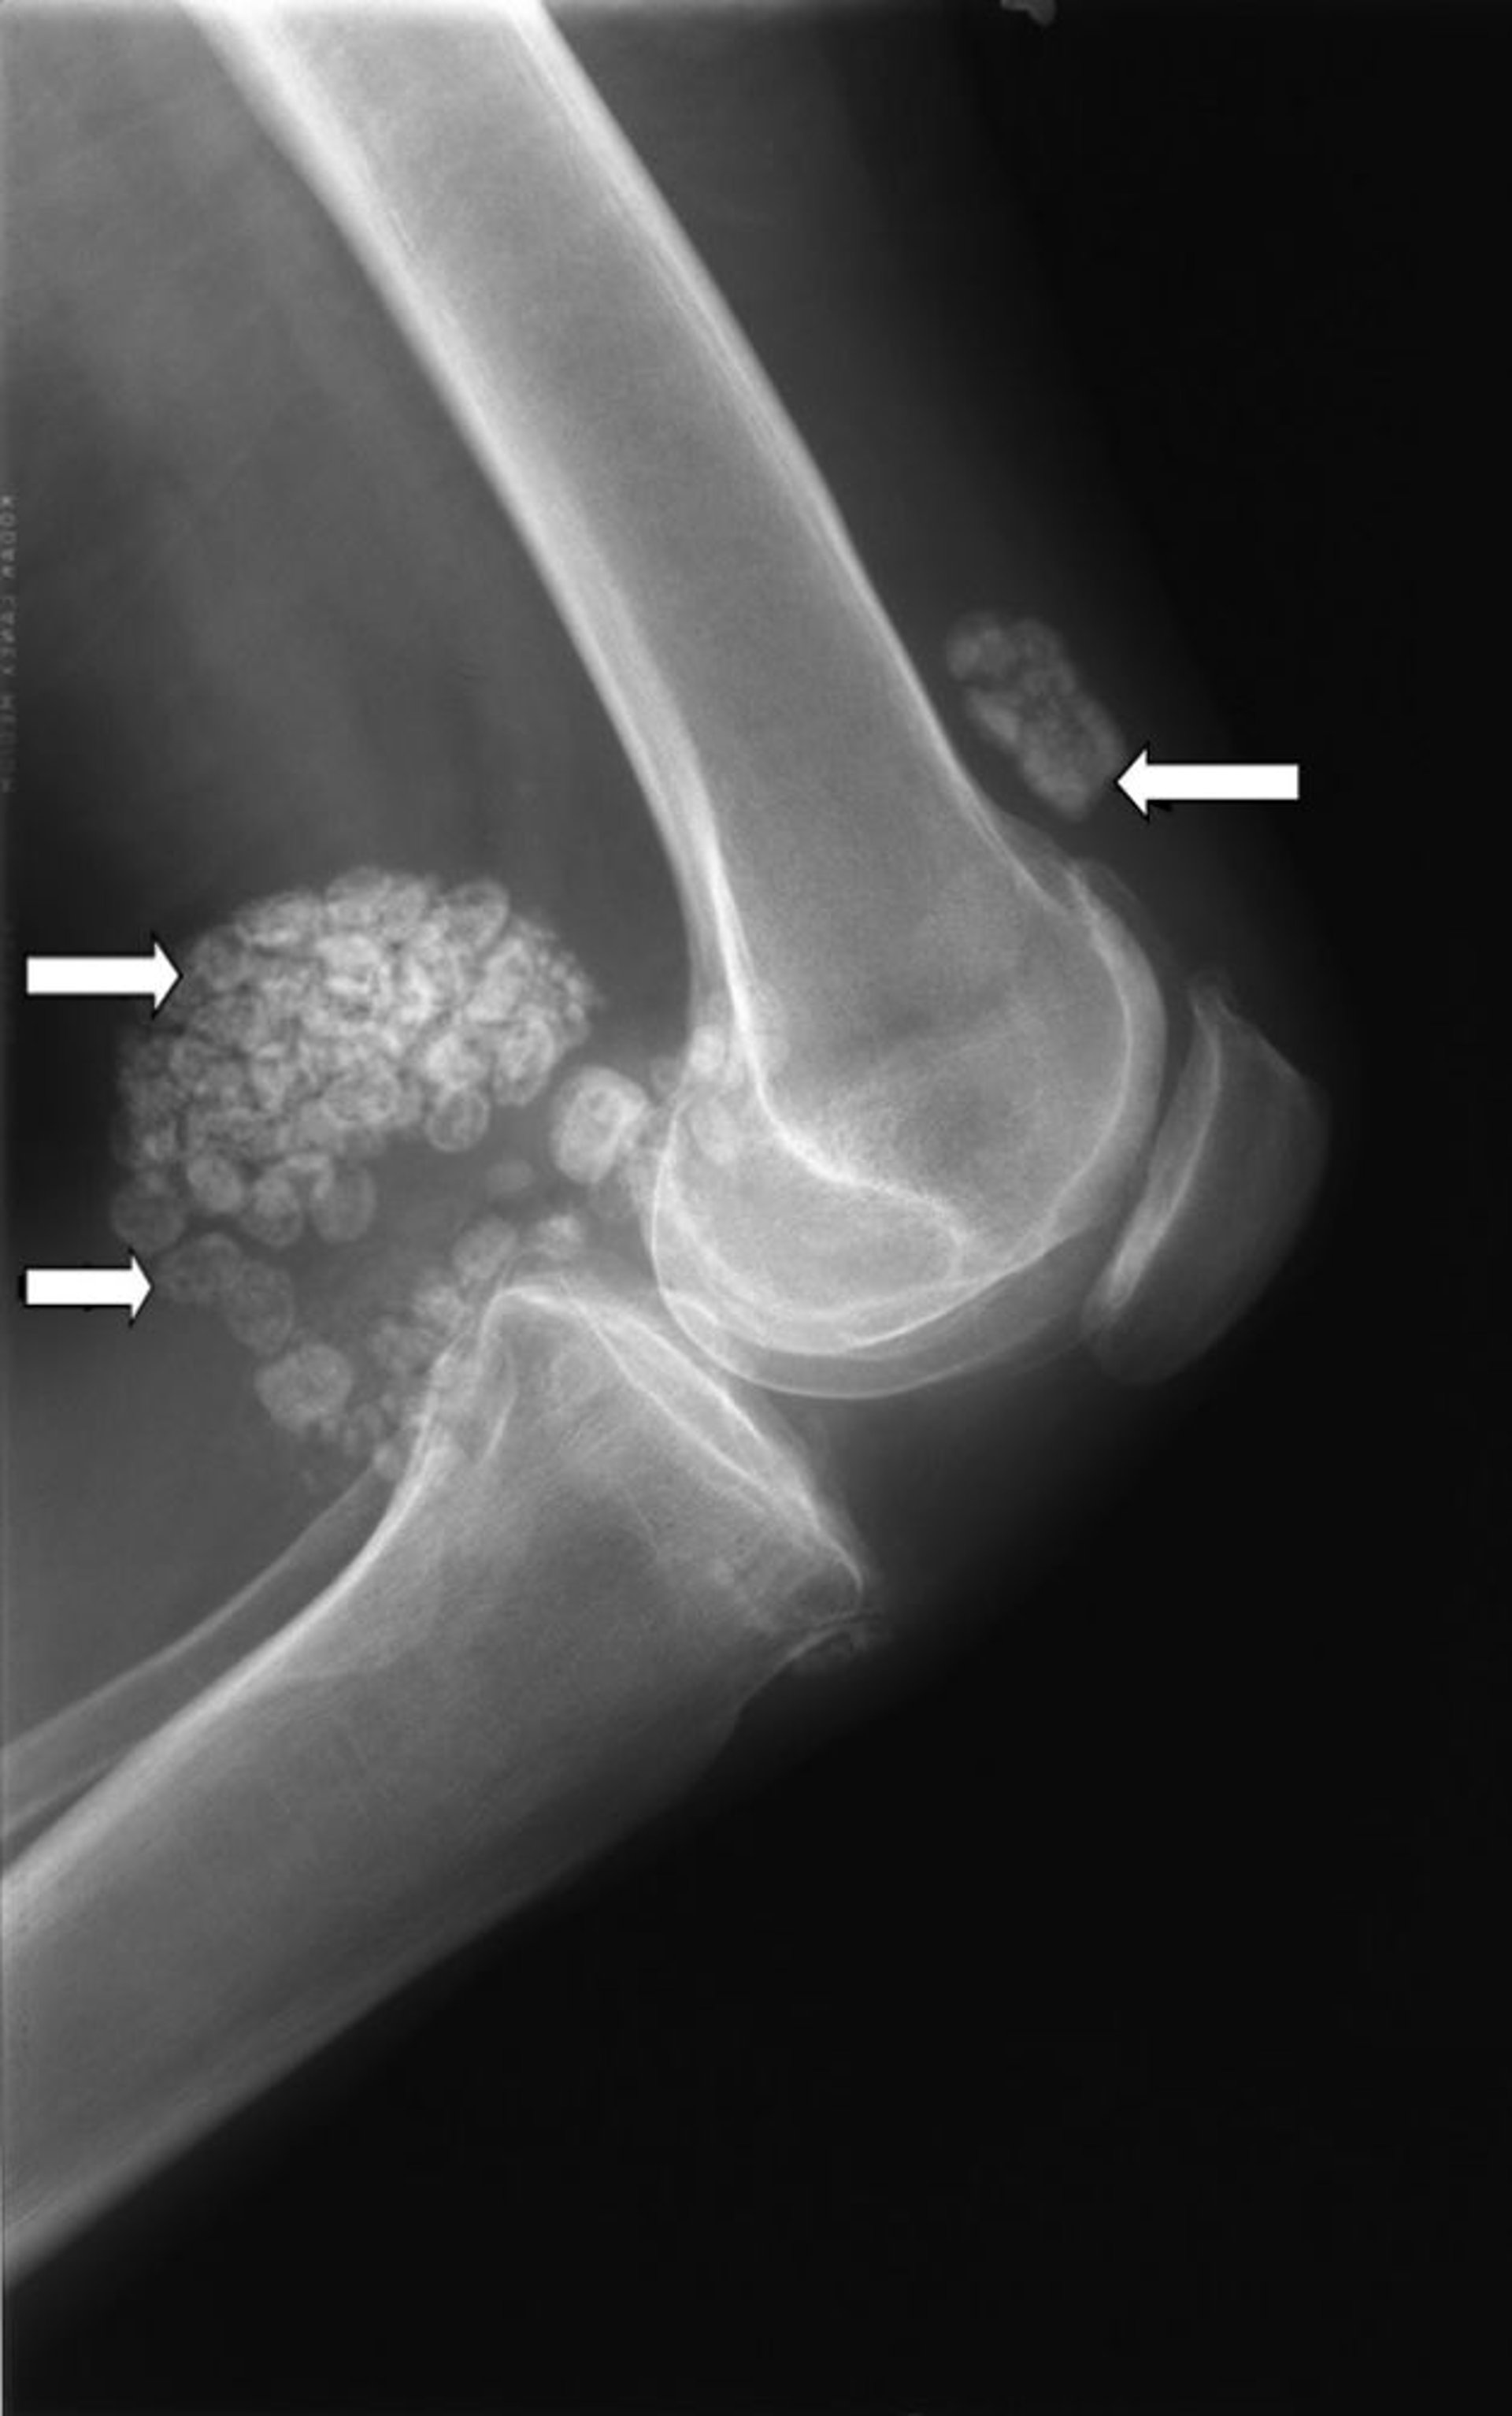

Radiografia del ginocchio che mostra numerosi nodi di cartilagine (frecce) noti come condromatosi sinoviale.

Per gentile concessione di Michael J. Joyce, MD e Hakan Ilaslan, MD.